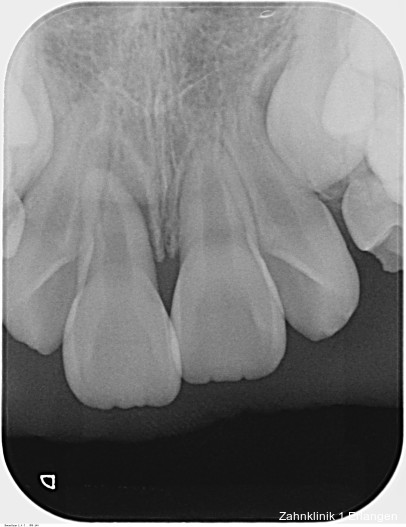

Zu den wesentlichen diagnostischen Verfahren, die zur Erfassung des Pulpastatus herangezogen werden, gehören neben der Inspektion und der röntgenologischen Bildgebung die Sensibilitätsprüfung sowie der Perkussionstest. Der Inspektion kommt insbesondere bei der Erstbehandlung eine wesentliche Rolle zu. Hierbei wird abgeklärt, ob es sich bei Zahnfrakturen um eine schmelzbegrenzte Verletzung handelt, ob das Dentin mitbetroffen und ob zusätzlich die Pulpa exponiert ist. Bei Dislokationsverletzungen wird das Ausmaß der Positionsveränderung erfasst und ob zusätzliche Gewebe wie Knochenstrukturen oder umliegende Weichgewebe betroffen sind. Auch können Farbveränderungen des Zahnes erfasst werden. Die Röntgendiagnostik zum Zeitpunkt des Unfalles gibt Aufschluss über die Größe des Pulpenkavums und das Lumen des Wurzelkanals, den Stand des Wurzelwachstums und die periapikalen Verhältnisse. Des Weiteren finden sich möglicherweise Hinweise auf eine Wurzelfraktur.

Zu den Zahnfrakturen mit Pulpabeteiligung gehören die in das Dentin reichende unkomplizierte Kronenfraktur sowie die komplizierte Kronenfraktur mit Pulpaexposition. Rein schmelzbegrenzte Frakturen sind hinsichtlich des Pulpastatus als unkritisch einzuschätzen.1 Dislokationsverletzungen betreffen die Pulpa insofern, als das Gefäß-Nerv-Bündel je nach Ausprägung der Positionsveränderung gestaucht, gedehnt oder abgerissen sein kann. Bei Zähnen mit abgeschlossenem Wurzelwachstum geht man davon aus, dass spätestens ab einer Dislokation von 2 mm die Pulpa abgerissen wurde, was die zeitnahe Einleitung der Wurzelkanalbehandlung notwendig macht.2, 3 Bei geringer ausgeprägter Dislokation kommt den Nachkontrollen eine wesentliche Rolle zu, bei denen jeweils dem Pulpastatus besonderes Augenmerk zukommen sollte, um eine Pulpanekrose frühzeitig zu detektieren.